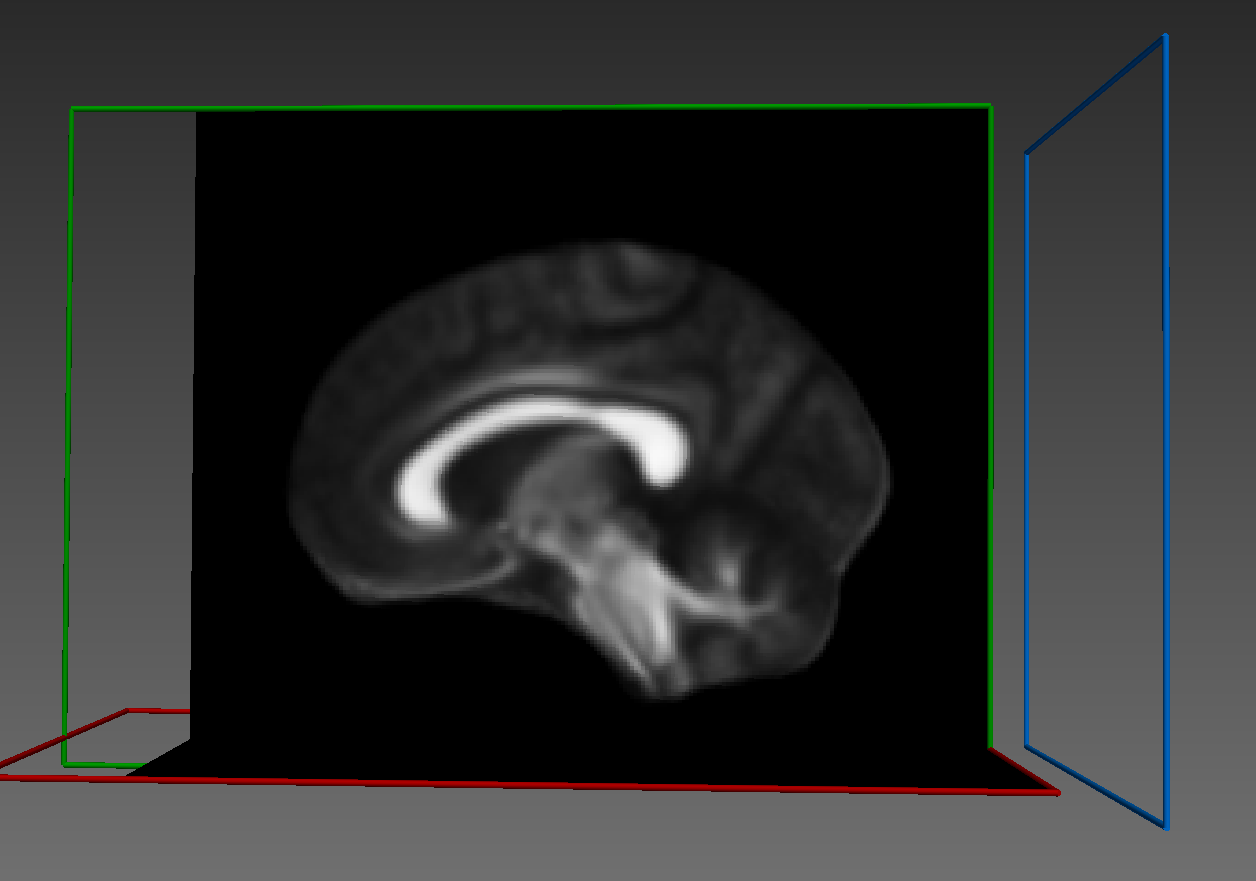

I am trying to nonlinearly register two FA images (derived from diffusion MRI). I am particularly interested in the affine map and warp nifti file that ANTspy registration generates. I apply the transformations and save my moved file. when I load the file in any other viewer (eg: MI-Brain), the output FA image is flipped and not correctly aligned with the fixed FA file.

Results look good when visualized inside the same notebook. However, when I save the warped image to nifti file, it does not align in any other viewer. (I tried saving as ants image and also like this mywarpedimage.to_nibabel() but in all cases same results)

Some sort of flipping. I tried changing the co-ordinate system of ants images as you can see commented lines in the code above. I tried using reorient_image2() function to have data in RAS before registration or even after registration. But in all cases, it gives me the same results.

On a side note, I tried everything, registering two images of the same size, dimensions, voxel sizes, etc. In all cases, my final output is flipped or not in the same space.